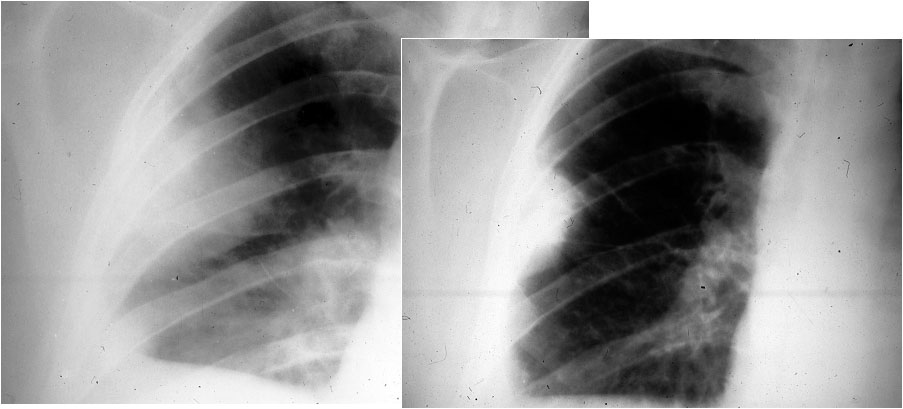

SIGNO DE LA JOROBA DE HAMPTON

Opacidad en cuña con base de contacto pleural, generalmente sin broncograma aéreo, que corresponde a infarto pulmonar. Aunque con frecuencia se localiza en el seno costofrénico lateral, puede encontrarse en otras localizaciones. La fotografía muestra una radiografía PA de tórax donde se observa una joroba de Hampton en el campo medio pulmonar derecho (flecha).

SIGNO DE WESTERMARK

Signo de tromboembolismo en la radiografía de tórax, poco frecuente de ver, que consiste en la asociación de hipodensidad del parénquima –causada por la hipovascularización del área afectada por el embolismo- y agrandamiento hiliar provocado por el alojamiento del émbolo en la arteria pulmonar (flecha). En la imagen la hipodensidad del parénquima afecta a los dos tercios superiores del pulmón derecho.